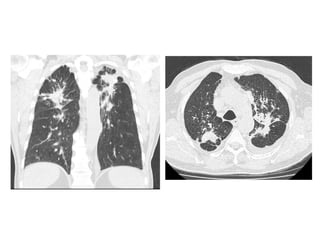

NSIP in a 53-year-old man with mild dyspnea, coronal CT image shows

diffuse lung involvement consisting of peripherally located irregular

linear opacities with ground-glass opacities (arrows), small cystic

lesions are seen (arrowhead)

48-year-old woman with scleroderma, cough, and dyspnea and biopsy-proven

nonspecific interstitial pneumonia, high-resolution CT through lower lungs

shows scattered ground-glass opacities that are relatively symmetric in

distribution, accompanied by bronchiectasis, honeycombing is absent, note

dilated esophagus, finding associated with scleroderma